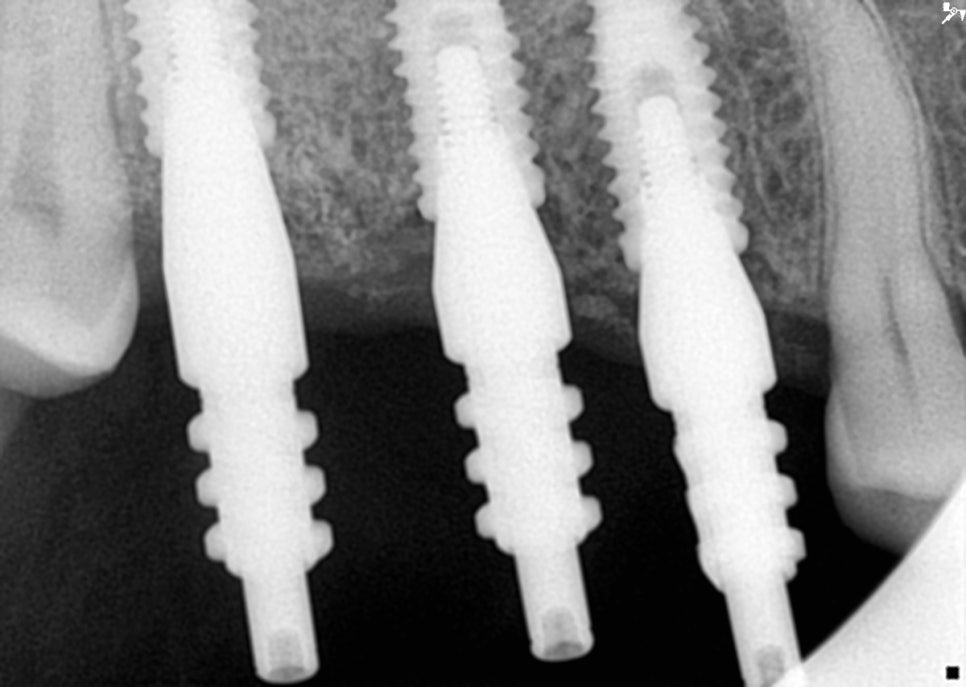

위쪽 3개 임플란트 식립 완료

임플란트 식립하는 구멍을 통해 상악동막을

거상을 하는 방식인데요.

아래쪽 임플란트

매우 정밀하게 진행을 해야합니다.

측방 접근법에 비해서는 침습자체가 적고

회복이 빠르다는 장점이 있습니다.

각 임플란트 부위마다 적절한 골이식재를

사용했고 인접 치아의 장축과 평행하게

정확한 각도로 식립하는 것이 중요하거든요.

초기에 고정력도 다행히도 양호하게

진행이 된 편이라 힐링 어버트먼트를

장착한 채로 골유착을 기다리기로

환자분에게 말씀드렸습니다.